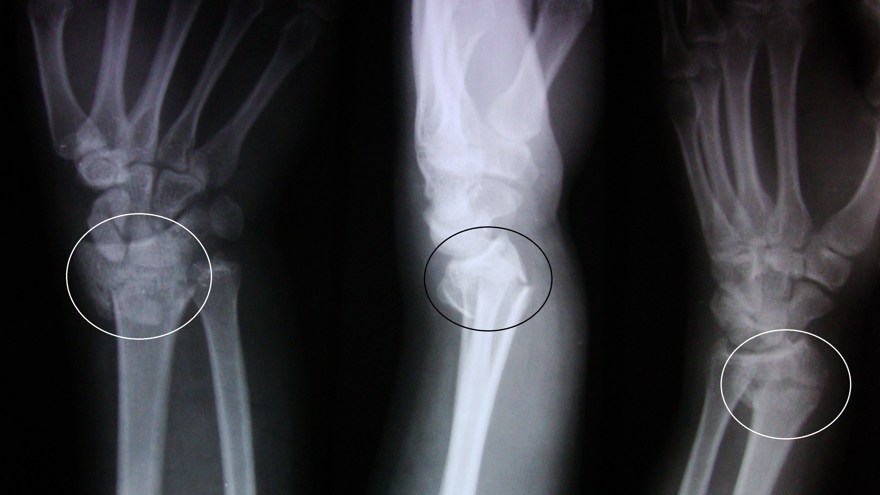

Distal radiusfraktur (handled)

Distal radiusfraktur är den vanligaste frakturen överhuvudtaget. Drabbar oftast kvinnor med osteoporotiskt skelett (fallskada inomhus eller utomhus vid halka). Högenergiskador i samband med trafikolyckor och sport drabbar vanligen yngre individer.

Hos yngre prioriteras frakturläge och frakturläkning, noggrann reposition (ofta öppet), säker retinering (ofta intern fixation) och adekvat immobilisering till frakturläkning. Hos äldre patienter med osteoporos finns ökad risk för svullnadskomplikationer och utveckling av CRPS (se komp I). Här läggs större tyngd på ödembehandling, handträning och handens totala funktion mer än läget på frakturen.

Olika distala radiusfrakturer

- Dorsal felställning: Colles fraktur

- Volar felställning: Smiths fraktur

- Volar felställning med intraartikulärt engagemang: Smith-Barton fraktur

Behandlingen bör individualiseras och bygga på klassificering av frakturen i olika svårighetsgrader.

Smith fraktur och Smith-Barton fraktur är ofta instabila och kräver rigid fixation, Smith-Barton oftast med volart anbringad frakturplatta. Colles fraktur kan ibland behandlas enklare, exempelvis med dorsal gipsskena. Denna fraktur dislocerar dorsalt, men även med axial kompression av radius. Graden av radiusförkortning anses påverka slutresultatet och kraftig förkortning bör därför reponeras.

Behandlingen kan utgå från ett klassificeringssystem, exempelvis Older som delar in frakturer i 4 typer beroende på initial felställning.

- Typ 1: liten felställning, radiusförkortning < 2 mm

- Typ 2: mer uttalad felställning, radiusförkortning 2-5 mm

- Typ 3: uttalad felställning med komminut fraktur av dorsala cortex, radiusförkortning > 5mm

- Typ 4: intraartikulär komminut fraktur med kraftig felställning.

Operationsindikation föreligger (om vital patient)

- Ulna+ 2-3 mm

- Dorsalbockning > 20° (mätt från normal/ursprungsläget)

- Hak i ledytan > 1-2 mm

Operation sker med volar platta.

Observera att det är vanligt med associerade ligamentskador (SL-ligament, LT-ligament, TFCC) i handleden vid komplicerade distala radiusfrakturer (högenergiskador) För att bedöma detta kan man behöva använda sig av artroskopi peroperativt.

Scaphoideumfraktur

Symtom

Palpationsömhet i fossa Tabatiére, smärta vid axialt kompression av tummen samt vid dorsalextension respektive radialdeviation av handleden.

Drabbar ofta yngre individer i samband med sportutövning eller efter annat kraftigt dorsalextensionsvåld. Frakturen är ofta svår att identifiera på slätröntgen varför upprepade undersökningar och/eller CT/MR kan behövas.

Scaphoideum är dåligt vaskulariserad och ofta läker dessa frakturer (ffa proximala polfrakturer) långsamt; 3 månader i gips är normaltid! Gipsen skall immobilisera tumbas, handled och begränsa armens pro-supination. Utebliven läkning (pseudartros) är relativt vanligt och risken ökar om frakturen inte immobiliseras från skadetillfället.

Bennetfraktur

Bennetfraktur är en intraartikulär luxationsfraktur genom basen av metacarpale I. Metacarpalbasen tenderar att luxera genom APL senans dragning i radiell-proxmal riktning. Frakturen behöver därför i princip alltid reponeras och immobiliseras internt med stift. Kan se väldig beskedlig ut på primära bilder men dislocerar succesivt genom senans dragning – klassificeras därför som ”lurig”.

Mekanism vid Bennetfraktur

Bennetfraktur där det ulnara fragmentet i basen på metkarpalen hålls kvar med hjälp av ligament i karpus. På grund av drag i abductor pollicis longus (APL) uppstår nästan alltid en diastas i frakturen. Diastasen i ledytan ger sekundärt artros. Dessa frakturer kräver således exakt fixation – vanligen i form av stift eller skruv.